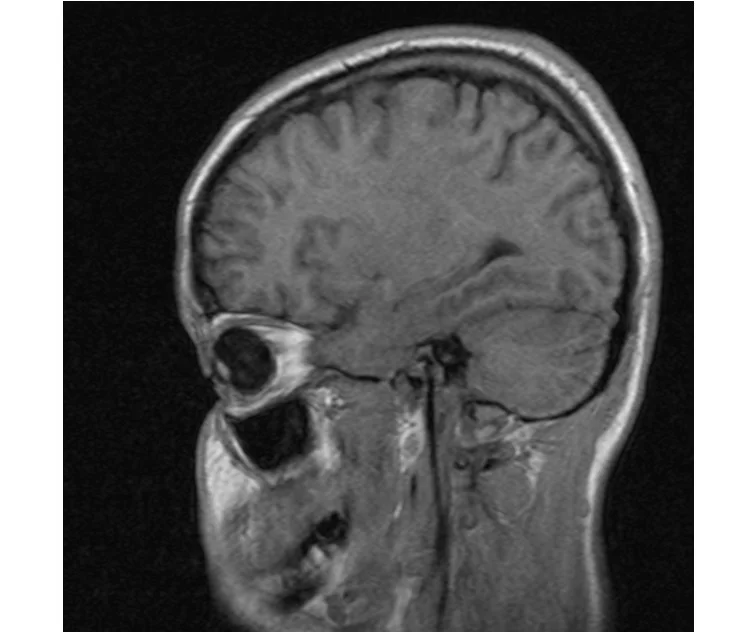

делал в обласной на siemense.В заключении выданом мне через 15мин.после мрт (легкая дегидрация)

Меня смутил факт выдачи заключения через 10мин(наверно они у них зарание напечатаные)я не медик.достаточно мимолётного взгляда на снимки?А вы видете на них гидроцефалию? Я лиш спросил куда идти с результатами томографии?и не хотел никого роздражать.

Я попросил взглянуть на снимки и сказать видна.ли на них гидроцефалия?или куда обратится за консультацией по этому вопросу?В мрт снимках наверно розбирается любой нервопатолог(я так предположил)

Я уже говорил, что независимо от того, есть на МРТ гидроцефалия или нет, лечиться тебе нужно только в том случае, если есть какие-либо проявления болезни, иначе на все эти анализы можешь забить... Но давай все-таки разберемся с томограммой.

Итак, с самого начала томограмма обозначала срез какого-либо органа на определенной глубине, позволяла заглянуть вовнутрь. При компьютерной томографии аппарат делает десятки срезов головного мозга в разных направлениях и из этого множества срезов он моделирует полноценное объемное изображение мозга в натуральную величину. Обрати внимание, компьютер работает не с этими миниатюрными изображениями, а с трехмерной моделью в масштабе 1:1. Эту модель вдоль и поперек анализирует суперсовременный компьютер, выполняющий миллионы операций в секунду. Только ***** может пытаться перепроверить компьютер, ведь человеку не хватит всей жизни чтобы проанализировать то, что компьютер с тобой сделал за 10 минут. Я хочу, чтобы ты это понял!

Ты разместл здесь несколько миниатюр и хочешь, чтобы врач по ним создал полноценное объемное изображение в натуральную величину, а потом осмотрел его со всех сторон и дал заключение? Но ведь это невозможно. Это просто насмешка над врачом, это издевательство над здравым смыслом. Принеси Букеру уменьшенный в 50 раз снимок зуба и спроси у него, в каком состоянии там корневые каналы. Или давай я дам тебе скрин со спутниковой карты города и попрошу тебя описать, какого цвета и какой модели запечатленная со спутника машина, какой у нее гос.номер, сколько в ней пассажиров, сколько из них мужчин и сколько женщин...